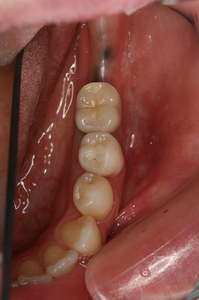

そして、インプラントと骨がしっかり結合した後に、インプラント上部構造(クラウン)を装着しました。手前の銀歯も治したいということで治療を行いました。

治療後の写真です。